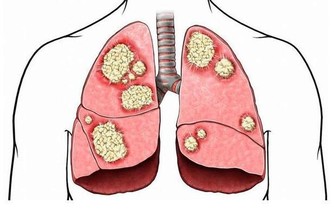

3. 儘早戒菸,遠離多個癌症

醫生指出,菸酒是打開癌症大門的推手,每天吸煙20支以上的人,患癌風險比不吸煙者高出若干倍,且女性比男性患癌風險更大。

吸煙不僅和肺癌有關,它還會讓人更易得胃癌、結直腸癌、宮頸癌、乳腺癌等癌症,都是鐵證如山。